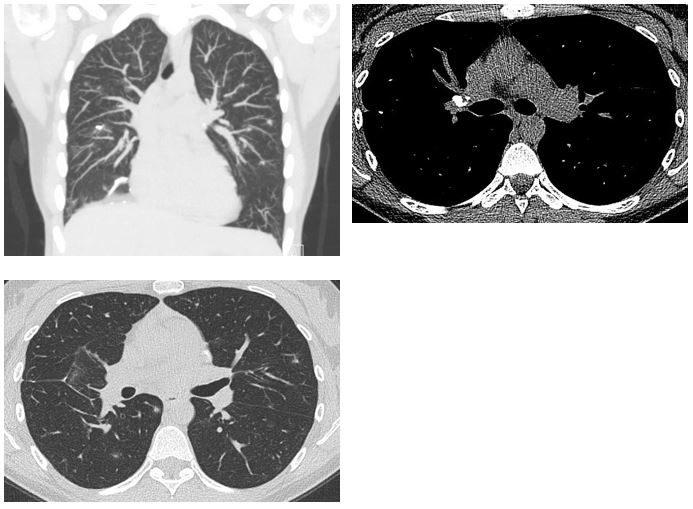

antinuclear cytoplasmic antibodies (ANCA). Representative CT scan images

of the chest are shown below (Figure 1).

Figure 1